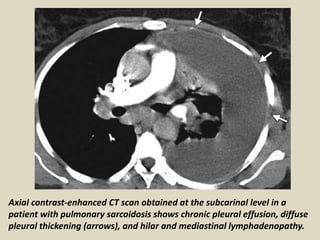

Axial contrast-enhanced CT scan obtained at the subcarinal level in a

patient with pulmonary sarcoidosis shows chronic pleural effusion, diffuse

pleural thickening (arrows), and hilar and mediastinal lymphadenopathy.